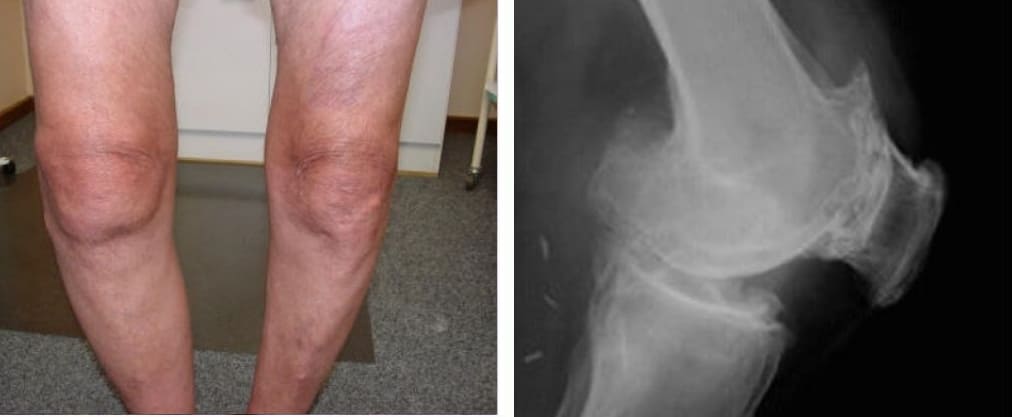

Mire estas fotografías. Esto es lo que les sucedió a todos los que ignoraron los síntomas. Hoy, estas personas están completamente sin esperanza, y muchos de ellos no tienen a quién acudir en busca de ayuda. ¿Realmente, quiere un destino así?

Atrofia y fuerte curvatura de las articulaciones de las rodillas, dolor constante y agudo incluso con los movimientos más leves.

Atrofia del cartílago de la rodilla, necrosis del tejido, destrucción completa de la articulación e inevitable amputación.